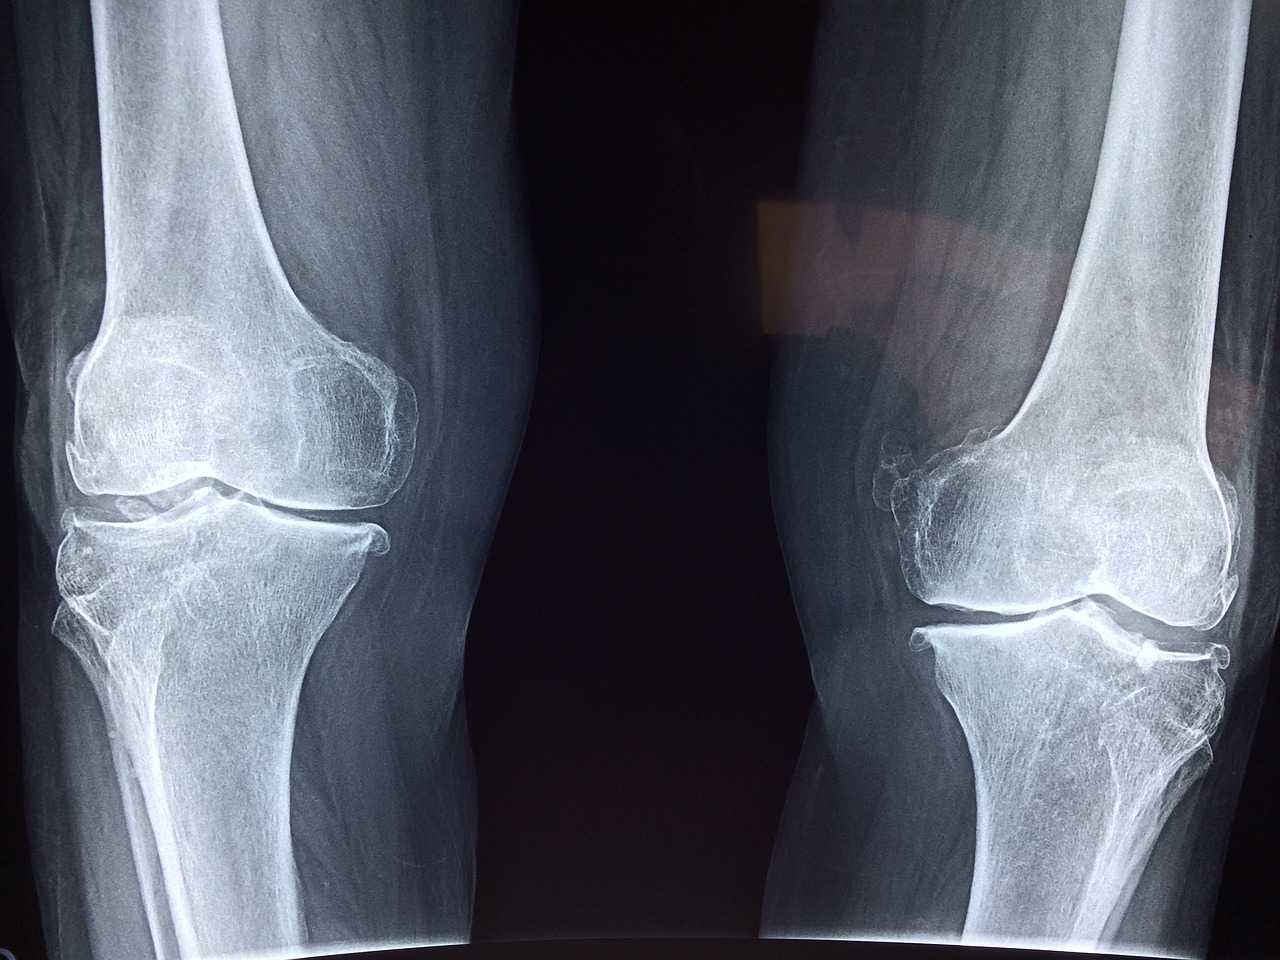

0 뼈 밀도 검사 (Bone Mineral Density, BMD 검사)

뼈 밀도 검사는 골다공증의 진단 및 위험 평가에 가장 일반적으로 사용되는 방법입니다. 이 검사는 X선, 초음파 또는 투과도 측정을 통해 뼈의 밀도를 측정합니다. 일반적으로 허리와 엉덩이 부위의 뼈 밀도를 측정합니다. 검사 결과는 T-점수 또는 Z-점수로 표시되며, 이를 통해 개인의 뼈 밀도가 평균 대비 얼마나 낮은지를 평가할 수 있습니다.

0 골조영상 검사 (Bone Imaging)

골조영상 검사는 뼈의 구조와 건강을 평가하기 위해 사용됩니다. 주로 X선, MRI (자기 공명 영상), CT (컴퓨터 단층 촬영) 등이 사용될 수 있습니다. 이러한 영상 검사를 통해 뼈의 손상, 골절, 골다공증과 관련된 기타 문제를 확인할 수 있습니다.